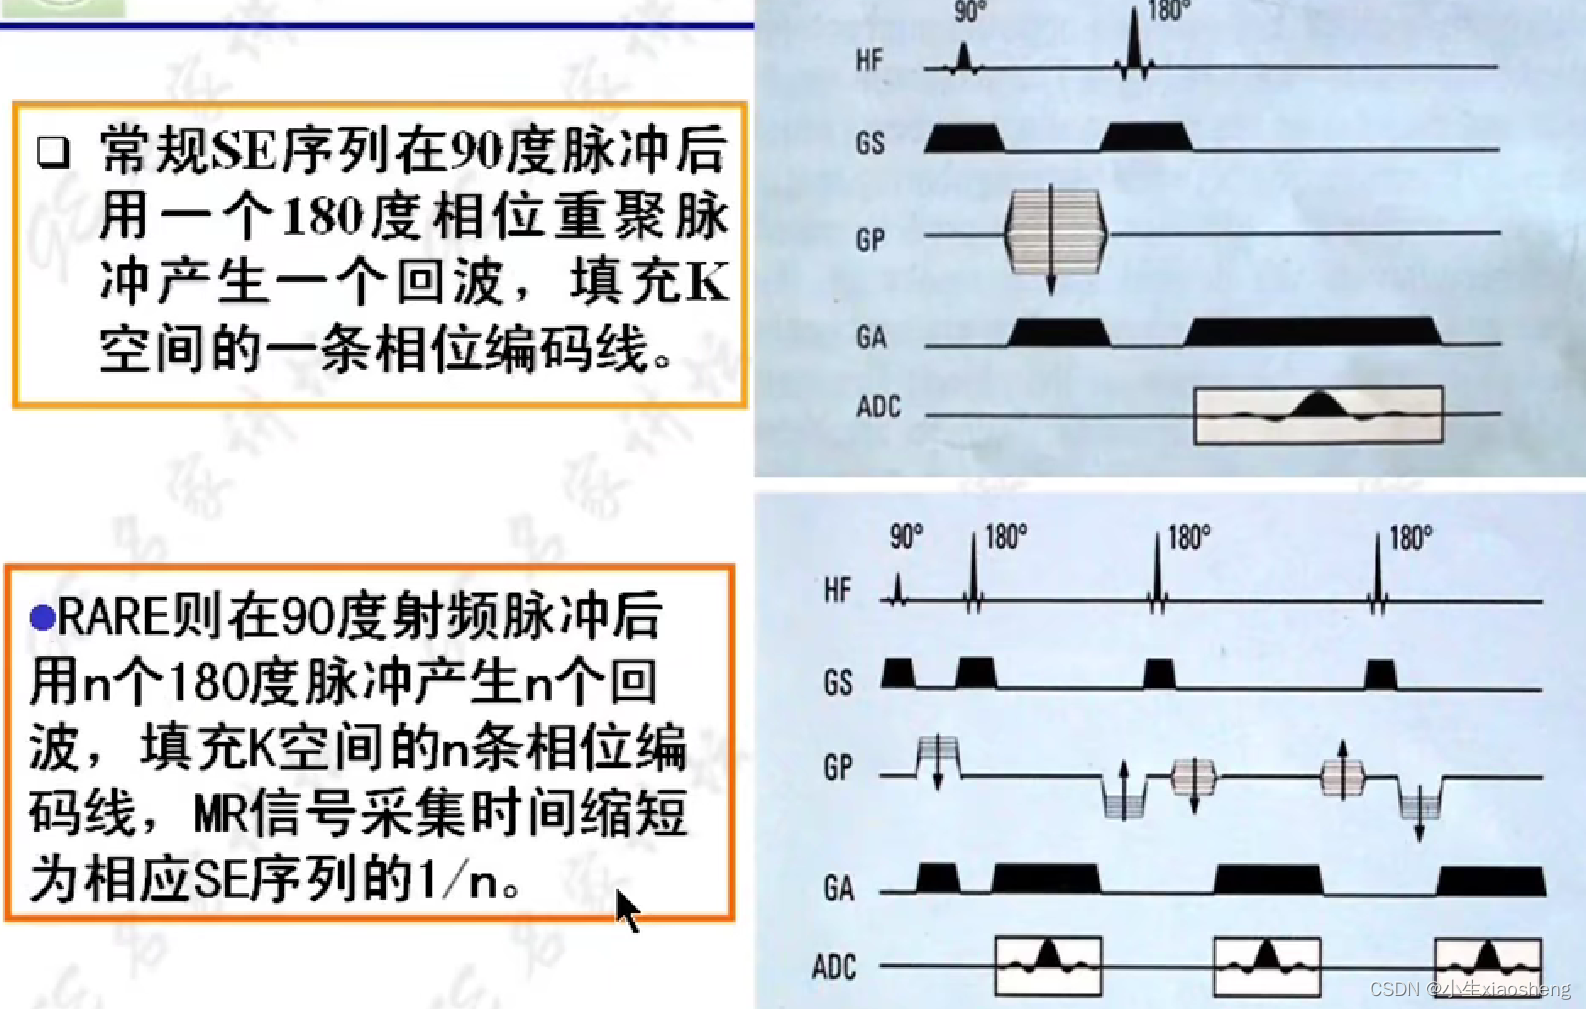

1.自旋回波序列SE

90度和180度共同来组成一条K空间线。

2.快速自旋回波及其衍生序列

因为这里有很多的180度,所以一次能填充很多K空间线。两个90度之间的时间还是叫做TR,180度的个数叫做ETL,90度到中间个数的180度叫做有效TE,两个180度之间的叫做ES。